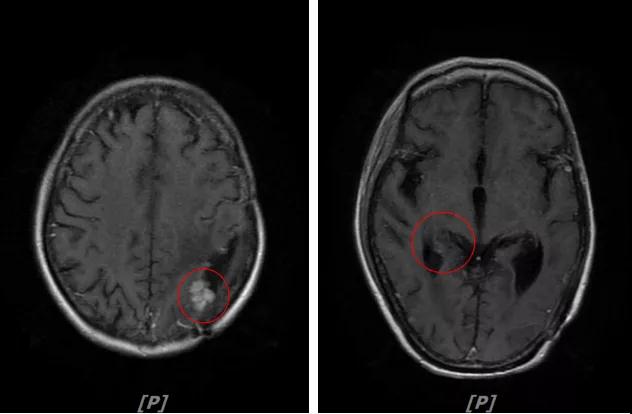

5. 病情第4次进展:2019年11月患者出现视野模糊等症状

头颅增强MR:左侧顶颞叶见片状T1WI低信号、T2WI高信号影,病灶大部信号接近脑脊液,增强后术区边缘左侧顶叶见结节状强化影,大小约10x8x11mm,较2019-03- 15MR老片大致相仿;右侧脑室三角区见结节样T1WI等低信号、T2WI不均匀稍高信号影,增强后不均匀明显强化,大小约24x18x20mm,较2019-03-15MR老片明显增大;两侧半卵圆区、侧脑室旁见较对称片状T1WI低信号、T2WI高信号影,增强后未见明显强化,较前片相仿;余脑室、脑池、脑沟大小形态可,中线结构向左偏移。

左顶颞叶转移瘤治疗后改变

右侧脑室三角区旁强化结节,较2019-03-15MR老片明显增大 左侧顶叶强化结节,较2019-03-15MR老片大致相仿

两侧脑室旁云絮状异常信号,考虑放疗后改变

患者三线治疗的PFS为14个月,2019年12月给四线治疗为“吡咯替尼+阿那曲唑”基础上联合曲妥珠单抗。

患者视野模糊等症状有所改善,继续定期复查。